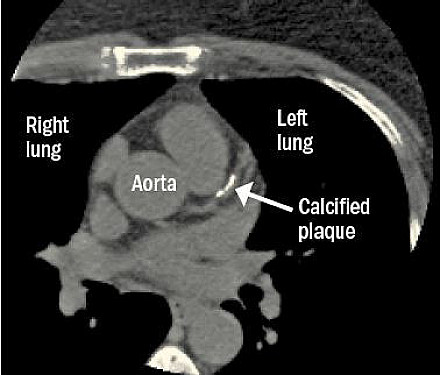

When you look for cancer, you might find heart disease